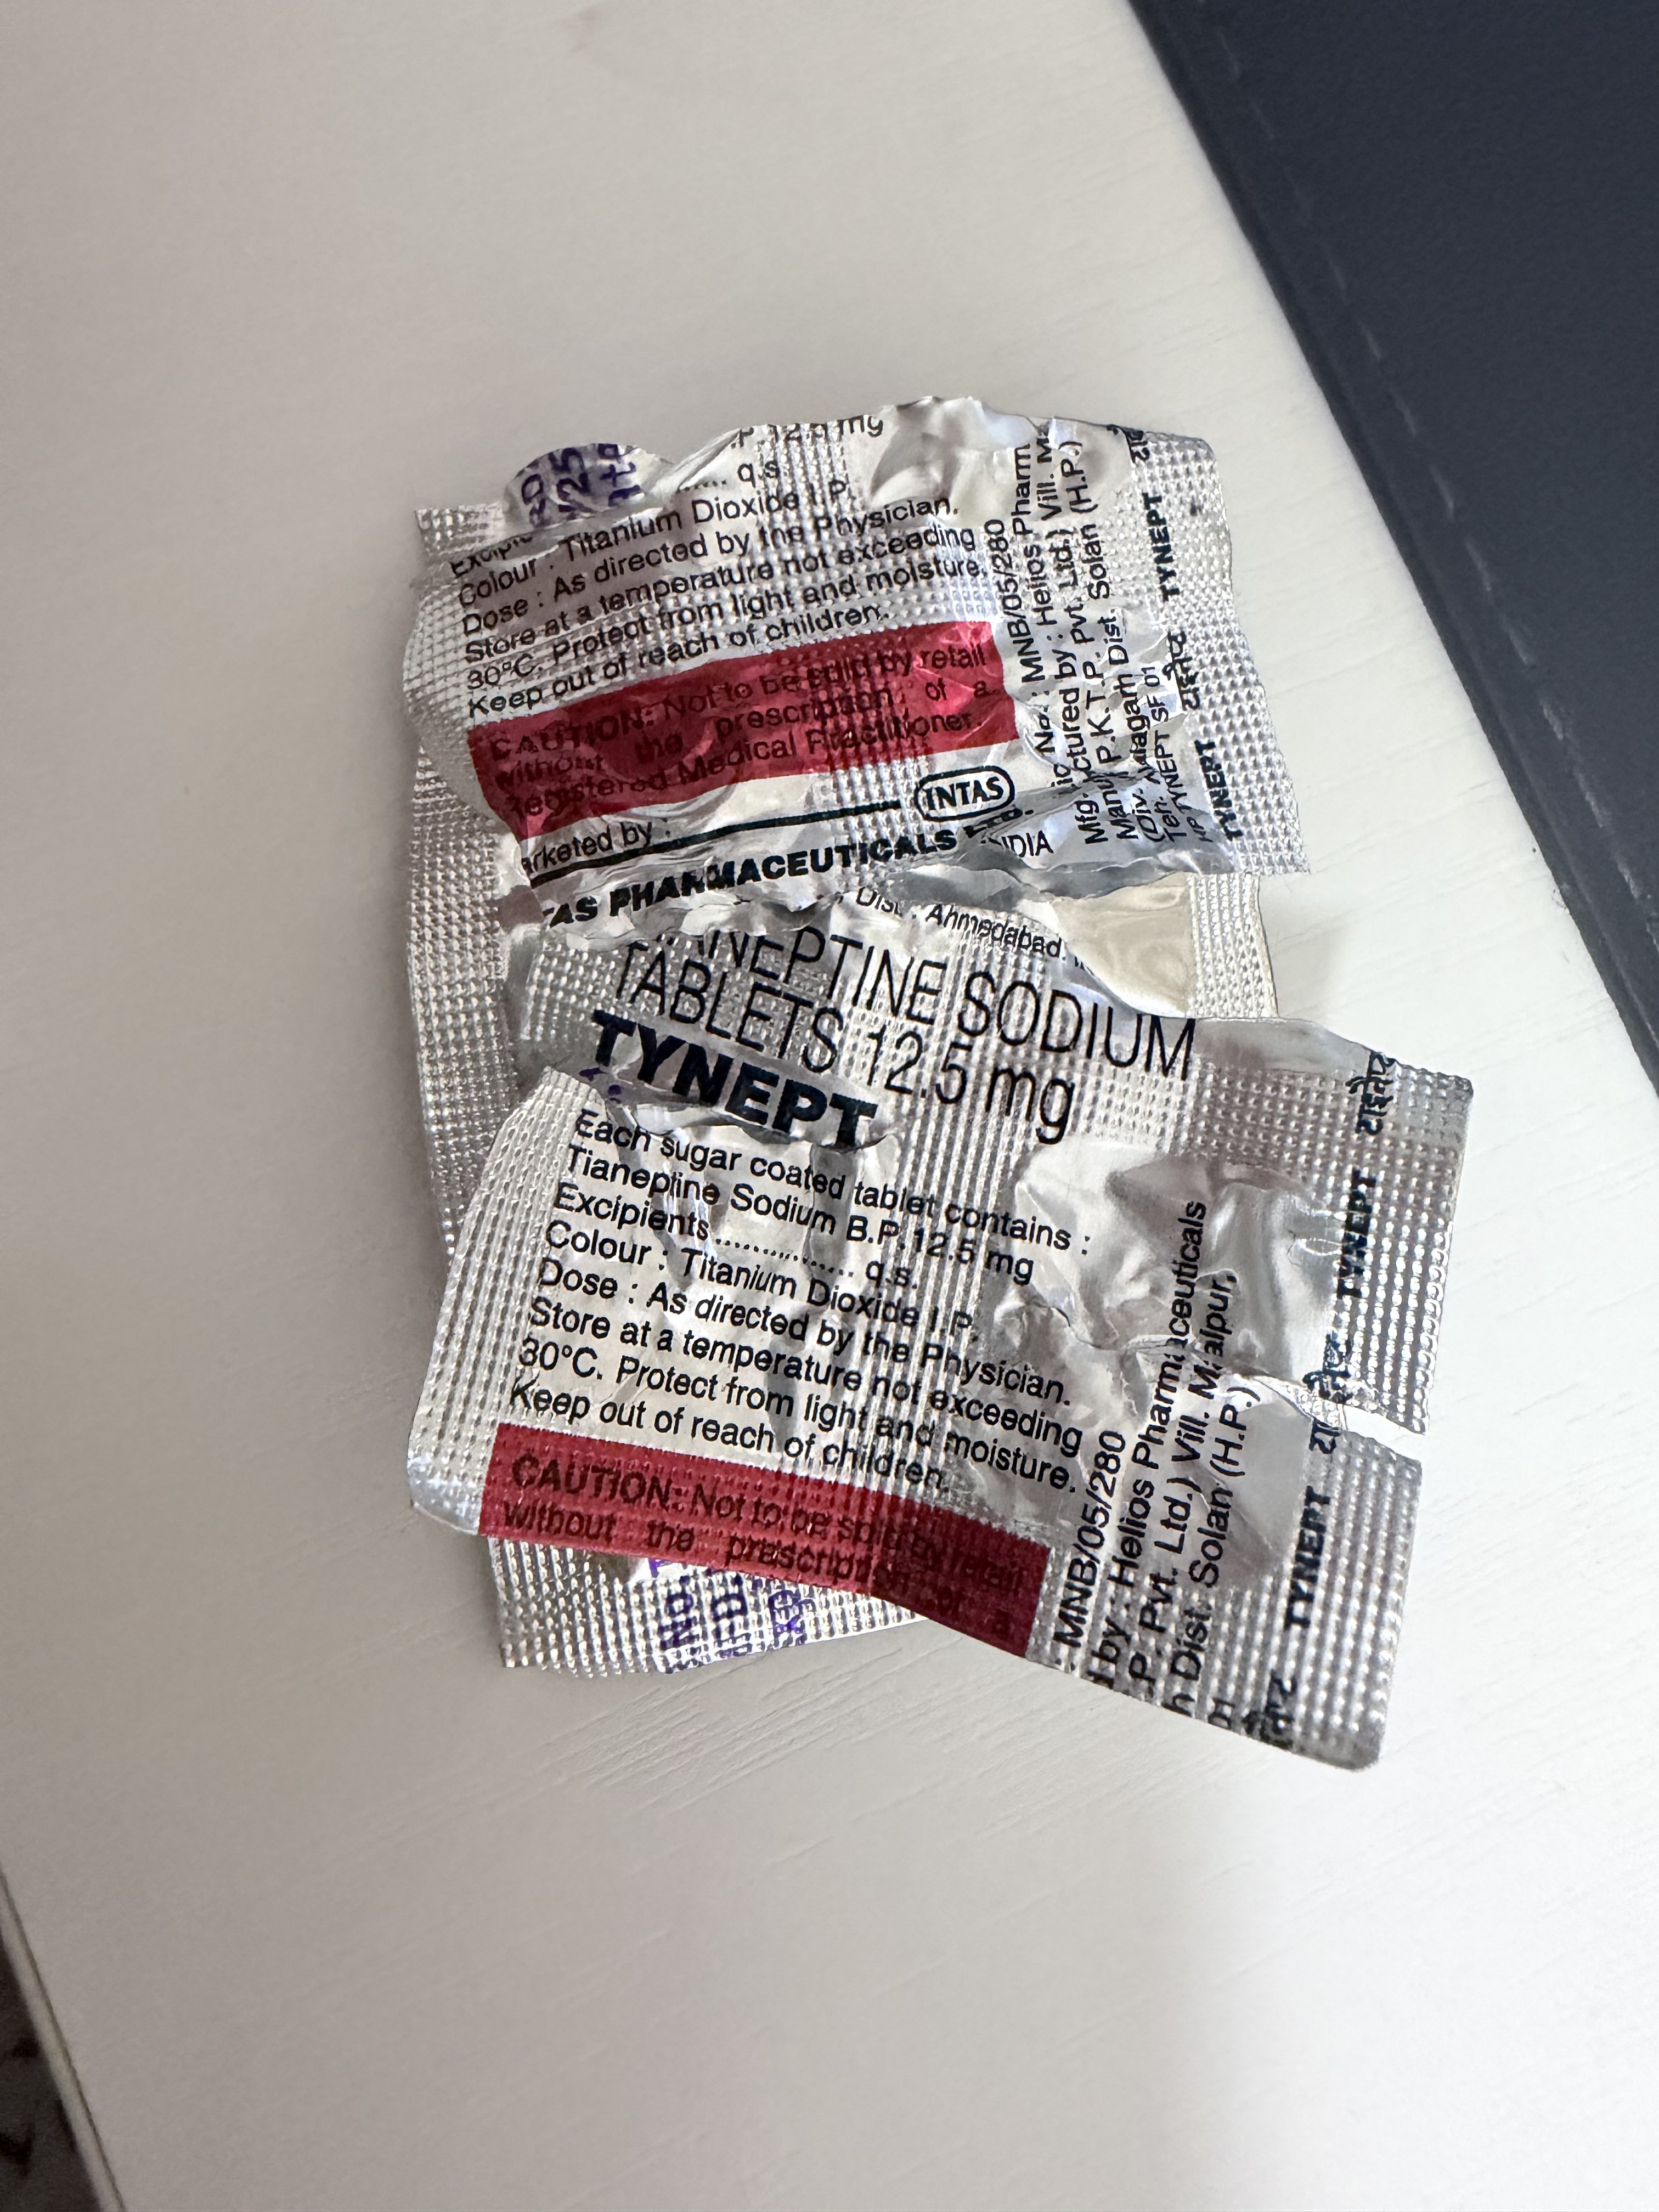

Tianeptine(半硫酸盐)

我只测试了几次相对偏高的剂量,其中一次在情绪波动很大的时候效果尤其出色,比起压制更像是一种能想通的感觉(?)

目前还没有观察到有情绪反弹的现象

但大剂量也会让延后出现的胃肠道副作用更明显,可能我又要滴定个合适的剂量范围了...哎

但在抗抑郁剂量下它间接调节谷氨酸 - 胆碱能 - HPA轴反馈的机制更多是有益的,虽然说阿片这块抗抑郁的作用现在也有研究,我感觉这个药还是低剂量比较划算🤔

鼠尾草~🌿 @SalviaSWC@AnIncandescence 半硫酸盐确实比钠作用时间长,适合神经保护,不适合娱乐()

炽烈已极 @AnIncandescence@SalviaSWC 本来我首选是钠盐的,但直觉上就是这个副作用要更恐怖一点(ó﹏ò。)💦

鼠尾草~🌿 @SalviaSWC@AnIncandescence 钠盐作用时间太短了,好像撤药反应比较也严重()

炽烈已极 @AnIncandescence@SalviaSWC 而且很贵!